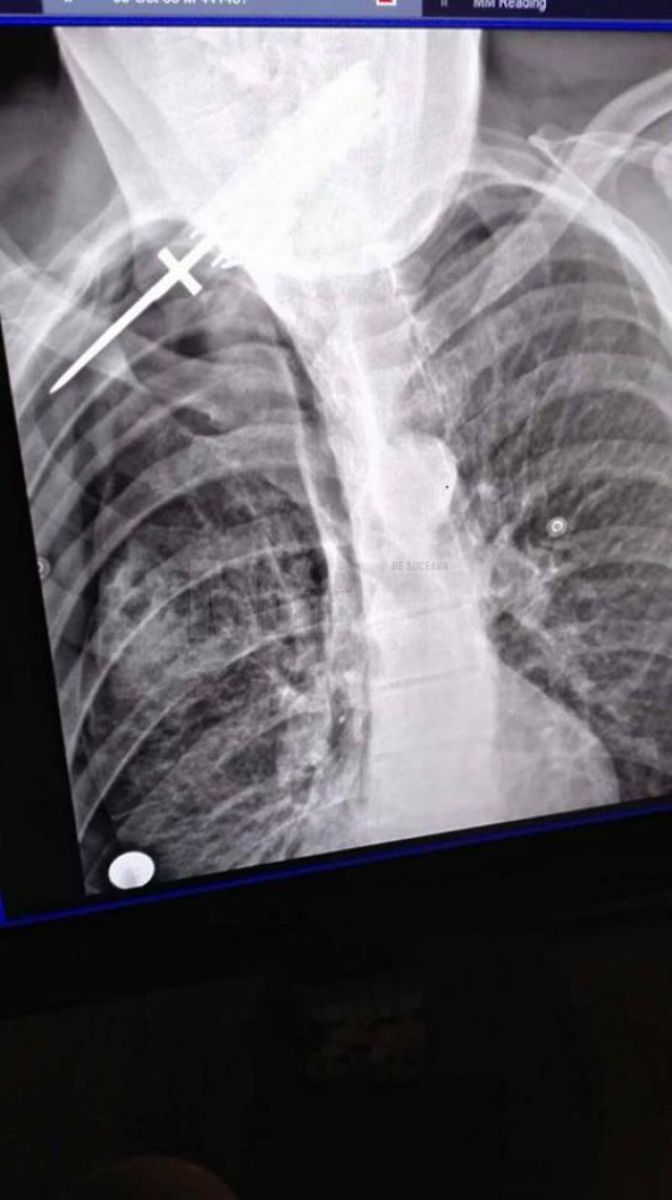

Neculai Feghiu a ajuns la Spitalul Judeţean Suceava cu cuţitul înfipt în spate. Leziunea a fost gravă, bărbatului fiindu-i afectat un plămân (pneumotorax şi hemotorax). Medicii legişti au stabilit că leziunile suferite de bărbat au necesitat 22-23 de zile de îngrijiri medicale.